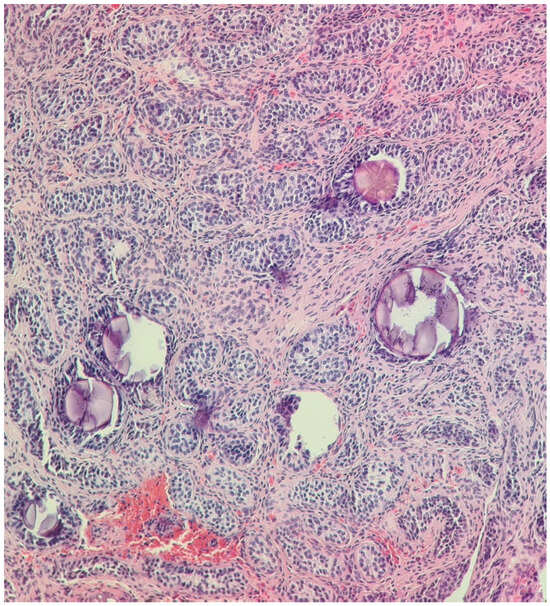

Figure 1.

Undescended left testis biopsy: immature testis consisting of small seminiferous tubules without lumen and composed of immature Sertoli cells, with no evidence of spermatogenesis (May 2014). H&E stain, 200× and 400×.

In February 2022, at the age of 13, following a routine ultrasound, a nodular image was discovered in the left inguinal region but outside the left inguinal canal, approximately 10–15 mm deep from the skin plane. The structure measured 15/10 mm and resembled a testis. The possibility of supernumerary gonads was raised. Another surgical intervention was performed and a biopsy from the suspected mass was retrieved. The histopathologic examination showed characteristics of immature prepubertal testis (Figure 4).

Figure 4.

Tumor in the inguinal region: Immature testis consisting of small seminiferous tubules composed of mature and immature Sertoli cells, with no evidence of spermatogenesis; scattered microliths. H&E stain, 100× and 200×.